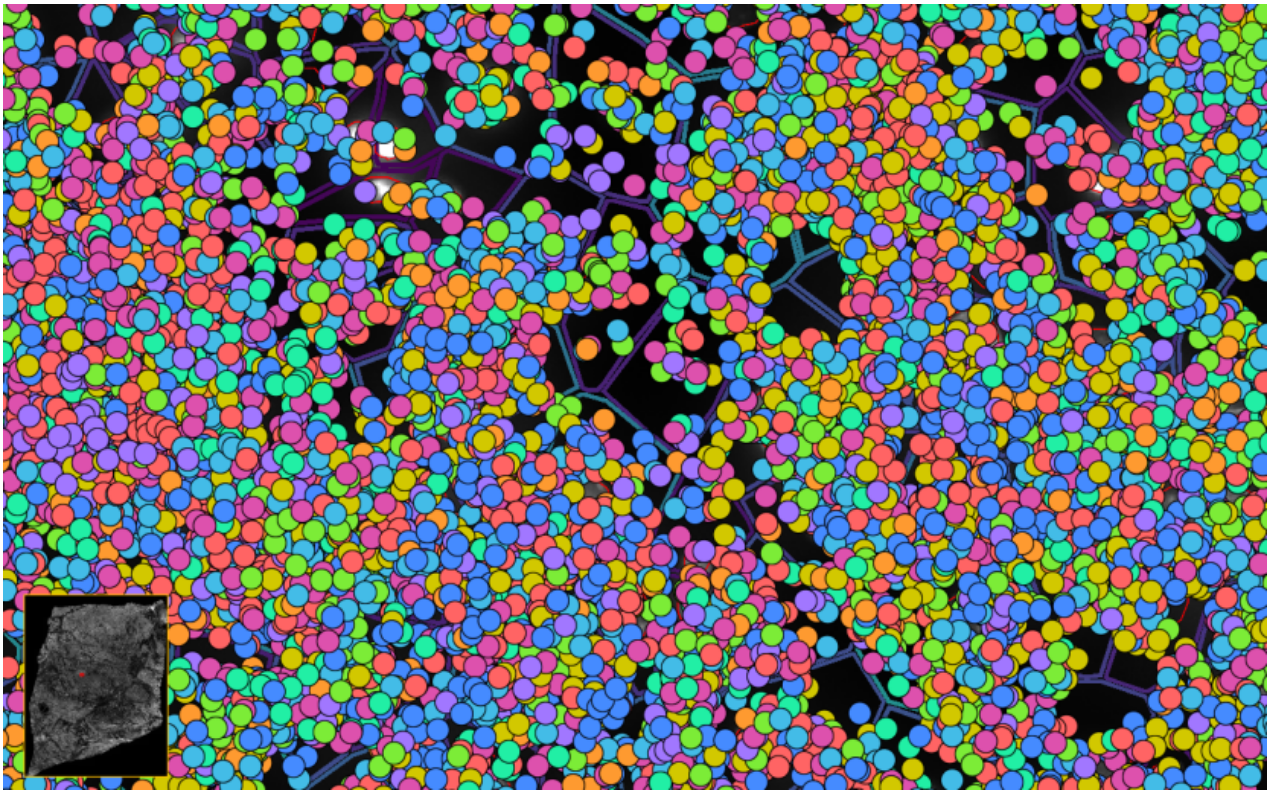

ͼ5£º½«×ªÂ¼±¾·ÖÅä¸øÏ¸°û